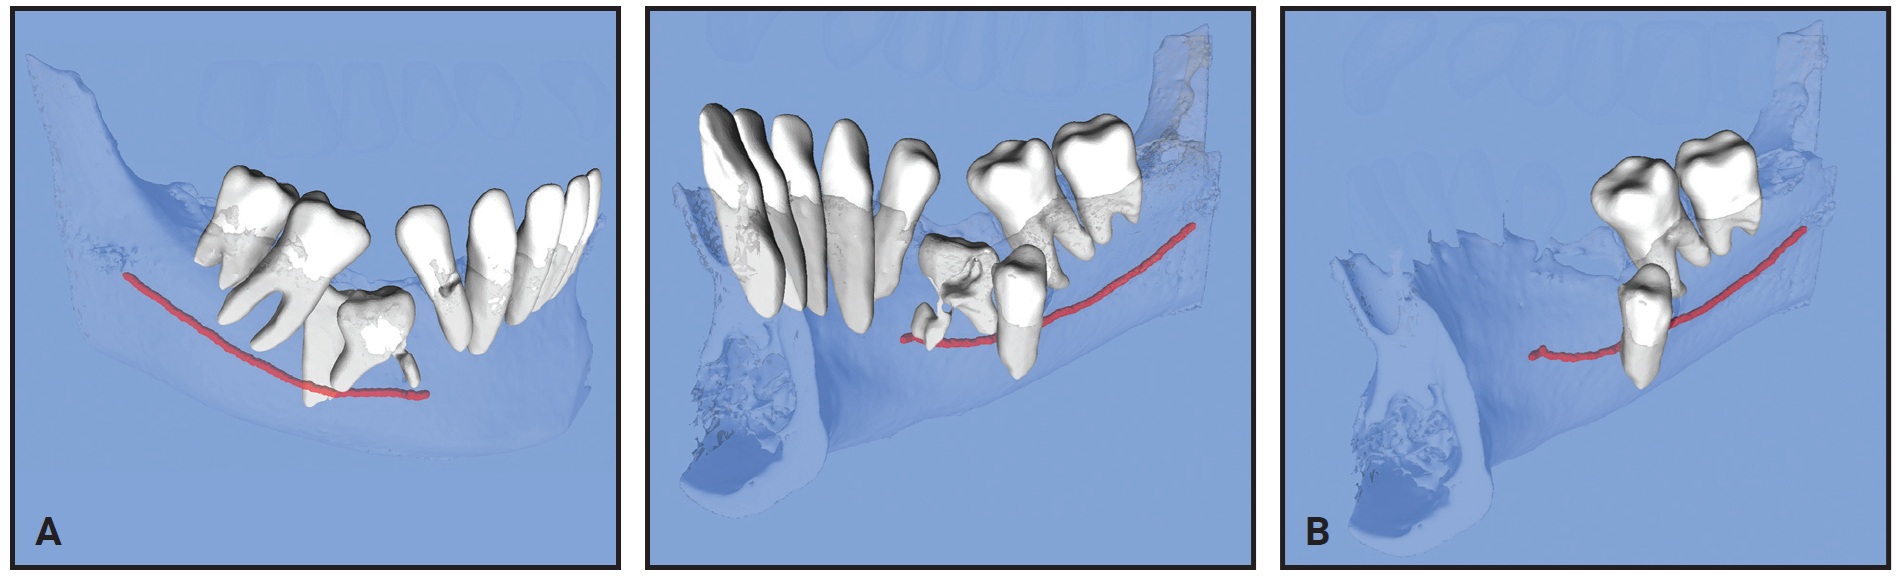

Fig. 2 Case 1. A. Pretreatment three-dimensional views from STL files. B. Views after virtual extraction of adjacent teeth and maxillary bone, showing severe resorption of lateral incisors. C. Upper lateral incisors after all other structures virtually hidden (images courtesy of CephX by Orca Dental AI).

Upon review of the 3D STL interactive models, it was clear that the resorption of the upper lateral incisors was more severe than initially suspected. The treatment plan was therefore revised to include extraction of the two upper lateral incisors and possibly the two lower second premolars (to be determined after the maxillary archform had been established). The extracted lateral incisors showed a similar morphology to those in the STL viewer (Fig. 3).

Fig. 3 Case 1. Actual extracted upper lateral incisors.